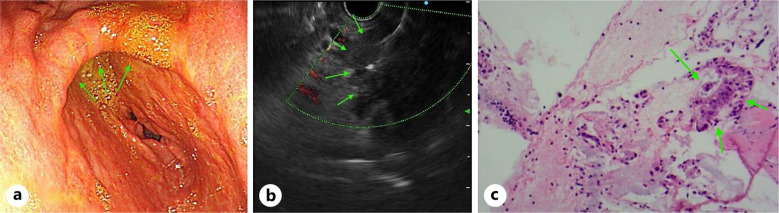

Case presentation: In this case, we report a 57-year-old man who presented with weight loss for 2 months. CT revealed a pancreatic mass. Endoscopic ultrasound biopsy of the pancreatic mass confirmed pancreatic adenocarcinoma. He refused treatment. Eight months later, he developed melena. CT revealed that the pancreatic mass had invaded the gastric wall. Gastric squamous cell carcinoma was confirmed by biopsy of gastric tissue under gastroscopy.

Conclusion: By observing the evolution process of this case, we found that the occurrence of gastric squamous cell carcinoma in this case was consistent with one of its pathogenesis: the theory of adenocarcinoma differentiating into squamous cell carcinoma. It provides certain clinical significance for the study of the mechanism of gastric squamous cell carcinoma.